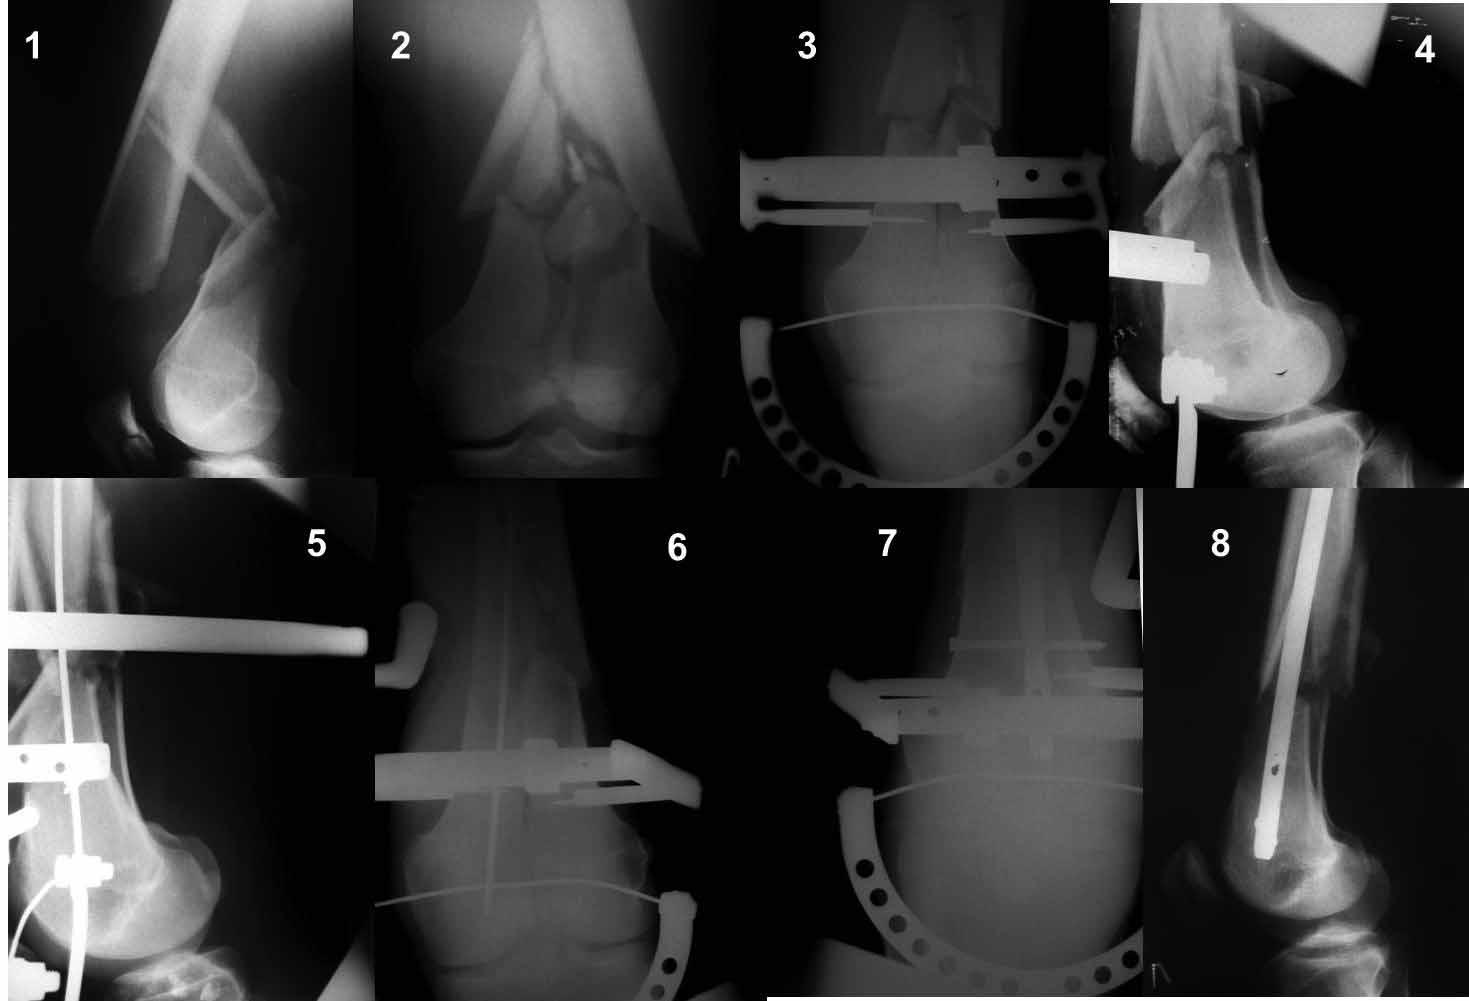

Ну зачем же так. Всё-таки считается "золотым стандартом". Во вложенном файле коллаж из сохранившихся фотографий одной из операций. Всё сделано закрыто и без ЭОПа.

Здесь пример медиальной пластины и латеральный комбинированный метод (у второго больного старый перелом тибиал плато, леченный где то и когда то)

В приложении пример недавней операции, C3, открытая репозиция, фиксация мыщелков спицами и винтами, ретроградный синтез большеберцовым гвоздем 10,5 мм диаметром, винты 5 мм.